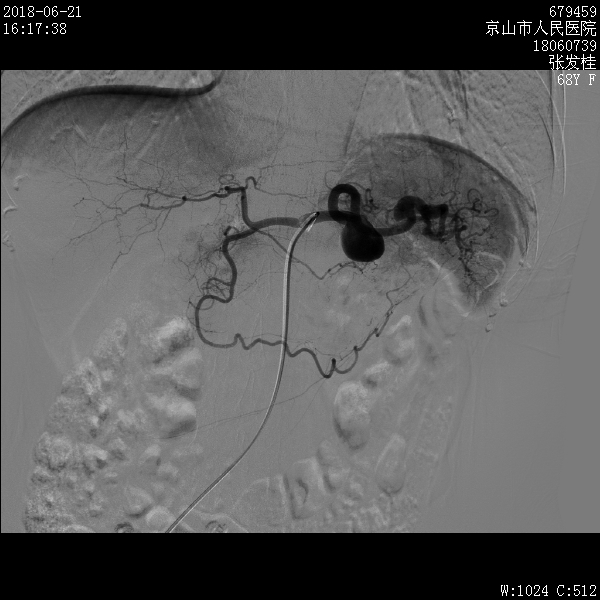

近日,放射介入科为一名脾动脉多发动脉瘤的老年患者成功实施了介入栓塞术,患者目前已康复出院。

脾动脉栓塞术是一种新的微创介入治疗技术,可应用于脾动脉瘤、脾脏出血(外伤、术后再发出血)、脾亢、脾肿瘤等多种疾病的治疗,是脾脏疾病微创治疗的新发展。